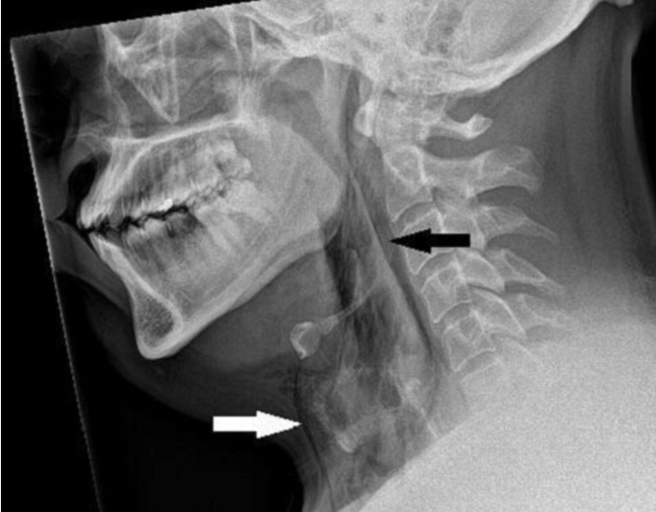

醫院檢查顯示男子的氣管出現一道撕裂傷。(圖/翻攝自BMJ官網)

這名30多歲男子被送到急診室時極度疼痛,頸部兩側腫脹且活動困難,醫師檢查時還可聽見微弱的劈啪聲,不過不影響呼吸、吞嚥與說話。頸部X光檢查顯示男子出現皮下氣腫,代表有空氣堵在皮膚最深層組織下方;電腦斷層掃描結果則顯示,穿孔部位在他第三和第四節頸椎之間,還有空氣堵塞在兩顆肺之間的胸腔裡。